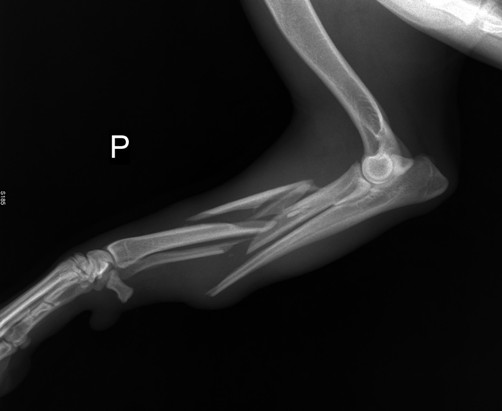

Mirella hat Jimi auf unseren Wunsch hin in die Tierklinik gebracht, damit sein Bein geröntgt und optimal versorgt werden kann. Der Bruch an seiner rechten Vorderpfote ist kompliziert, ein Splitterbruch an Elle und Speiche. Jimi war bei allen Untersuchungen sehr brav, obwohl

er starke Schmerzen hat. Durch seine liebenswerte Art hat er sofort alle Herzen des Klinik-personals im Sturm erorbert. Bereits für heute (14.06.) wurde die OP angesetzt, wobei der Bruch verschraubt wird.

Mirella hat uns die Röntgenaufnahmen von Jimi, vor und nach der OP, als Datei geschickt.

Sie schreibt : Die Aerzte haben gesagt, dass der Bruch kompliziert war. Ein Splitterbruch

ohne OP verheilt nicht. .Jimi hat die OP sehr gut verkraftet. Er ist stark , brav und laechelt.